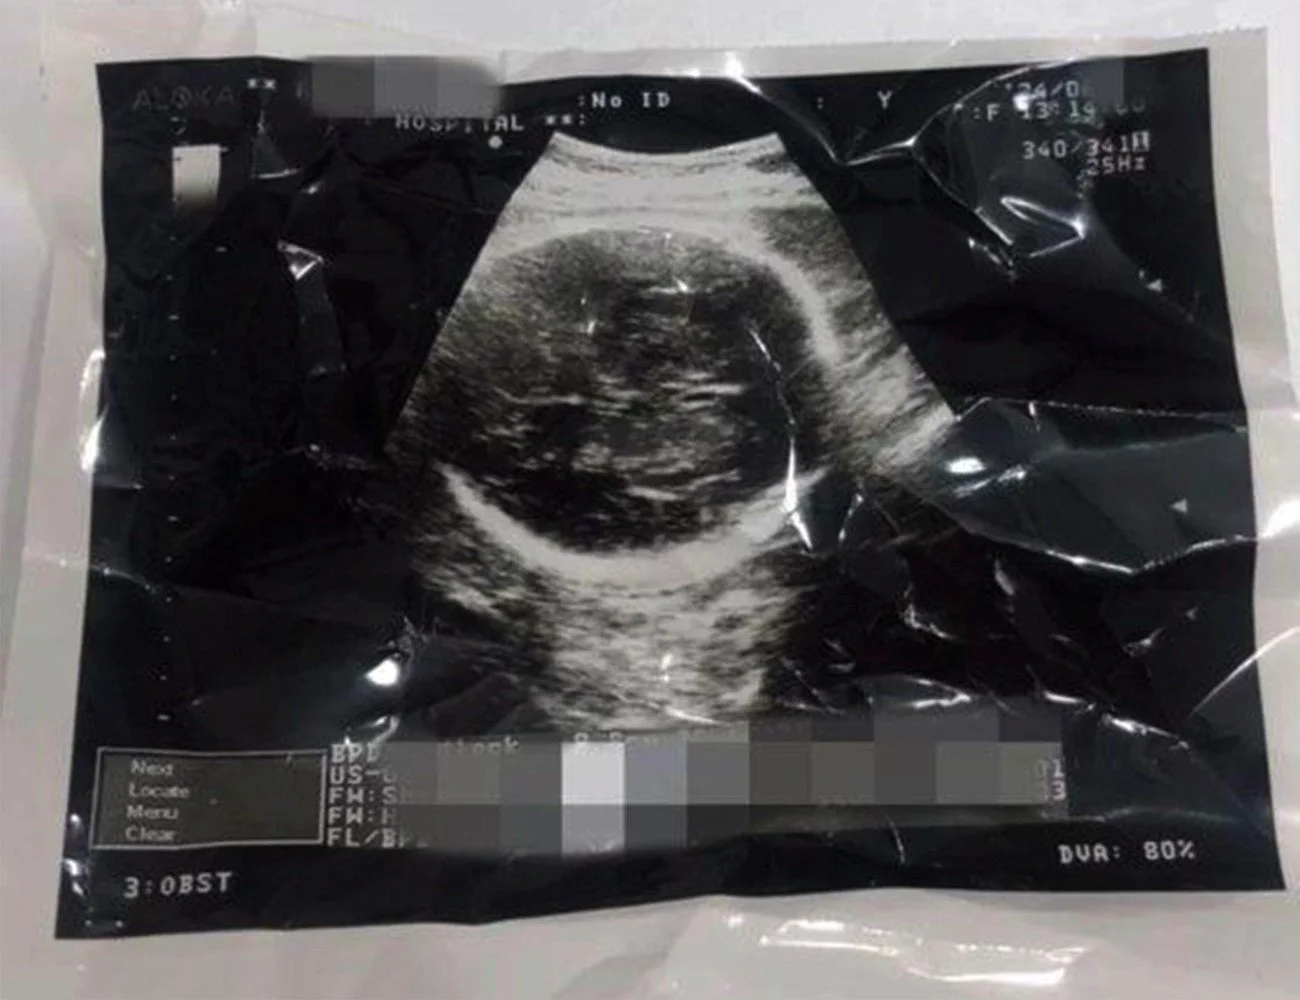

온라인 커뮤니티